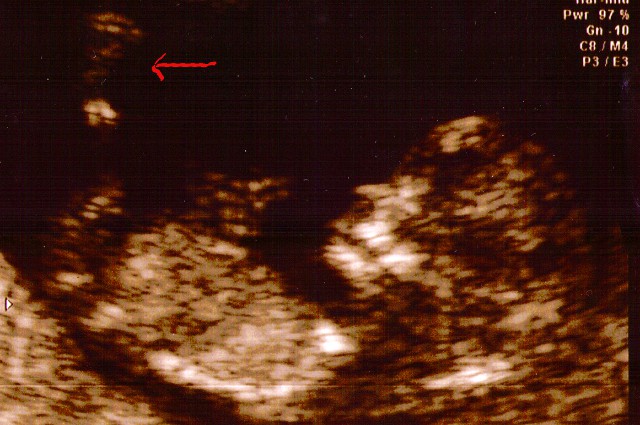

Love at first sight (part two) It's amazing what four weeks can mean when you are young (and you are, very much so). Last time, you were not much of a looker admittedly (though that meant nothing to me, of course). And here you are now, just a month later, with two arms, two legs and even a brain (that last one is important, hold on to it if you can). I think you have your mother's nose. She thinks you have mine. We'll see in about six months (the arrow points to your leg, not your nose). Everyone we know says that our lives will change - and I am sure they will. I am also sure that we will both be fine with that (watch me eat my words in seven months).